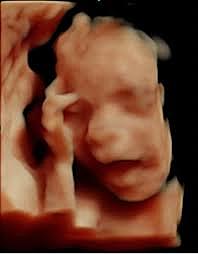

• Semana 12

27

Semana 12

Cuello bien definido, oído externo bien definido, saco vitelino se ha retraído, expulsión de meconio, ovarios descienden, sangre se puede coagular.

• Semana 13

28

Semana 13

no tiene huesos tal y como los entendemos nosotros. Y en realidad no los tendrá hasta la adolescencia, cuando pare su crecimiento. El cartílago empieza a osificarse

• Semana 14

29

Semana 14

las orejas del feto se encuentran implantadas a ambos lados de la cabeza y también los ojos se han acercado, ya se distingue el puente de la nariz. El cuello se ha alargado y el mentón ya no descansa sobre el pecho.